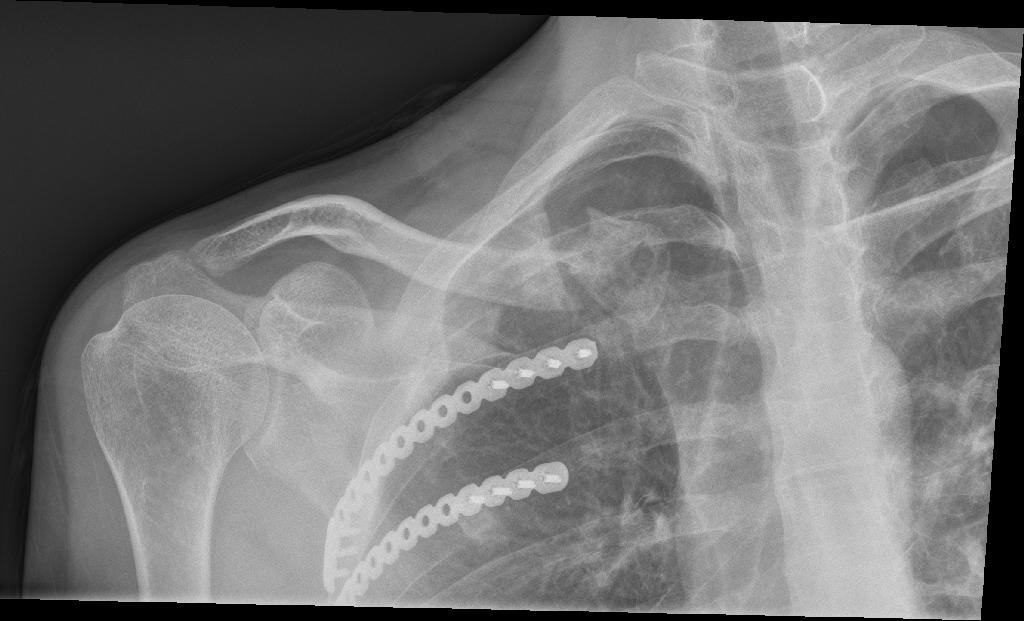

From news reports, Stephen was scooped up onto the hood of an SUV that was barreling down the bridge, flew into the air, thrown into the back end of a bus, and was dumped onto the road, hitting his head, fracturing his skull, neck, back, ribs, puncturing his lung – and shattering bones in his left leg, ripping part of his calf open.